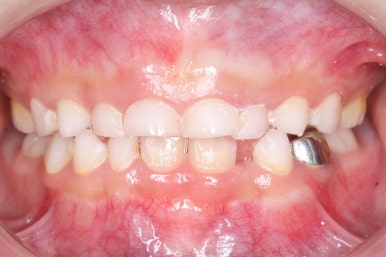

부산어린이치아교정 키다리아저씨치과에 처음 내원하셨을 당시의 입안의 모습입니다. 네 군데 모두 어금니는 보이지 않습니다.

입 안에서 문제점이 발견되지 않는 경우 일이 커지는 경우가 많은데 이번 환자분은 X-ray를 찍어봄으로써 문제를 조기에 발견하고 치료를 할 수 있었습니다.

X-ray 촬영이 신의 한수 였던 것이지요.

어금니를 개선해 주는 치료만 해주면 되는 경우였고, 현재 입 안에서 해당 어금니가 일부라도 보이지 않기 때문에 여러 가지 치료옵션을 염두에 두고 몇 달 간격으로 체크해 보기로 하였습니다.